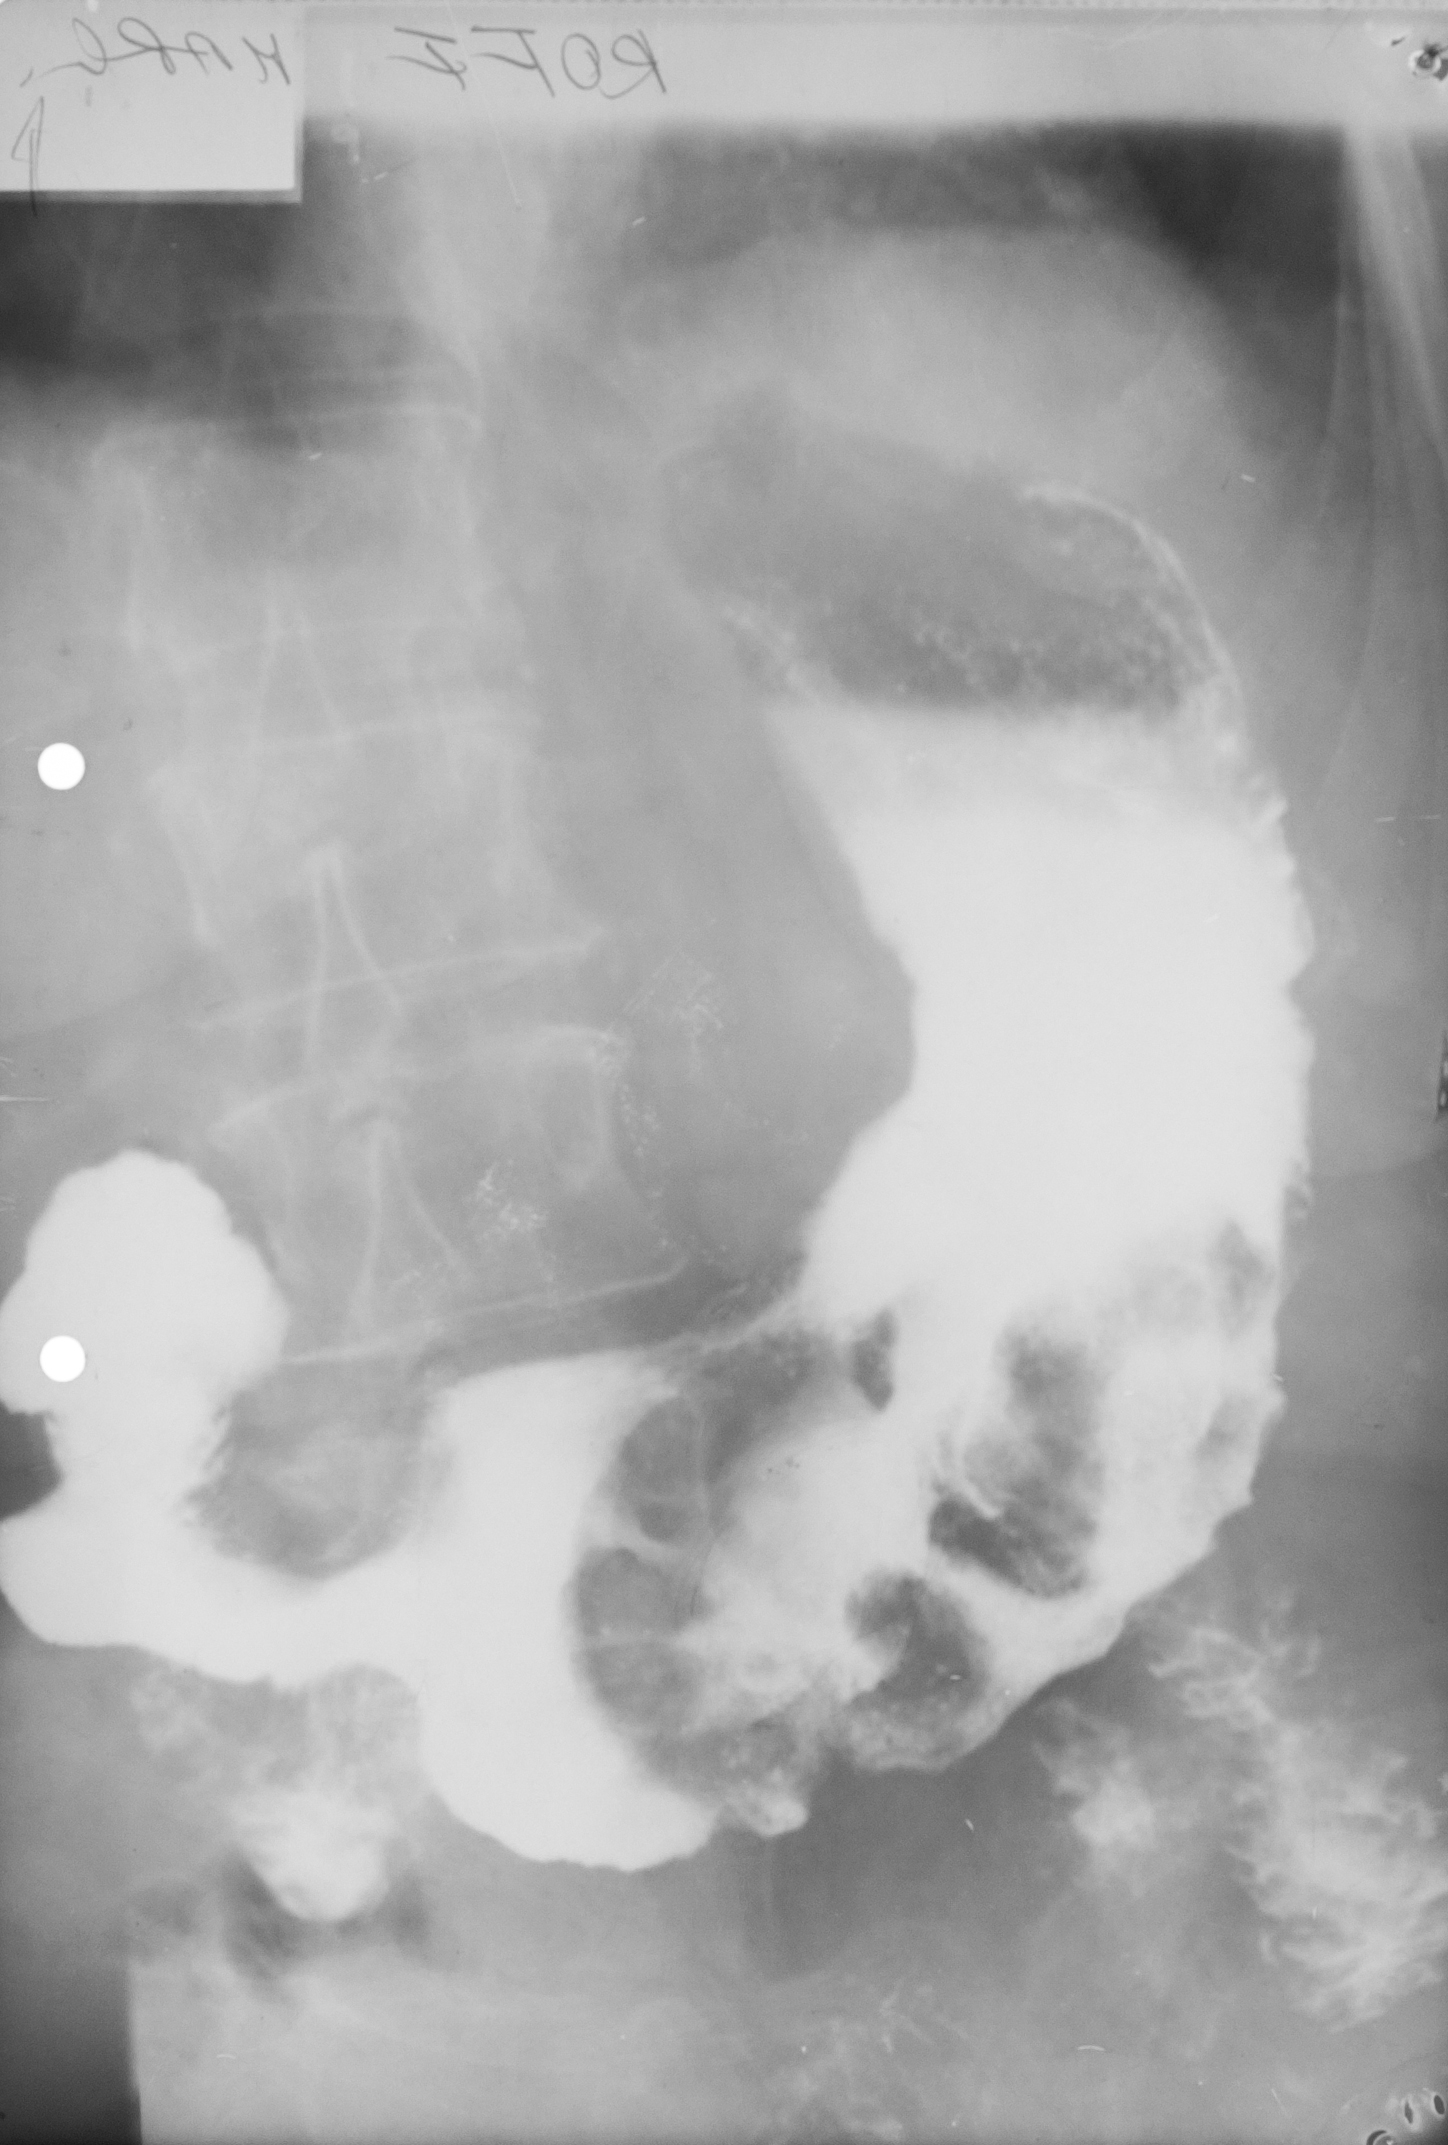

NIȘĂ ÎN LACUNĂ

Examen baritat al corpului gastric

Se observă defecte de umplere,adică dislocuirea substanței de contrast de ceva ce se găsește în lumenul stomacului și anume o masa parenchimatoasă cu contur polilobat.

Cel mai probabil este un proces neoplazic vegetativ de dimensiuni mari,care are la nivelul ei și o ulcerație.Imaginea se numește nișă în lacună.

NIȘA MALIGNĂ ÎN REGIUNEA ANTRALĂ

Nișa malignă este mai mult lată decât adâncă și nu iese din conturul corpului gastric.

Ulcerația este în perete,dar nu iese din conturul peretelui gastric.

ULCERAȚIE CRONICĂ

Se observă,în urma tranzitului baritat,bulbul duodenal cu incizuri la nivelul curburilor,având aspect de treflă,caracteristic pentru ulcerațiile cronice

:NEOPLAZIE INFILTRATIVĂ

Tranzit baritat.Se observă o îngustare semnificativă a lumenului la nivel antral,dând aspect de antru amputat.Nu sunt vizibile pliurile de mucoasă,deci este vorba de o neoplazie infiltrativă.

NIȘĂ LA NIVELUL BULBULUI DUODENAL

Tranzit baritat.La nivelul bulbului duodenal se află o pată persistentă de substanță de contrast,captată la nivelul unei nișe

NIȘĂ DE TIP MALIGN

Nișă de tip malign mai mult lată decât adâncă,situate în regiunea antrală cu pliuri de mucoasă ce converg până în craterul nișei

Tranzit baritat.Bulbul duodenal cu o pată ce persistă pe una din fețele bulbului.Avem de a face cu o nișă de dimensiuni mari la nivelul bulbului

LIMFOM GASTRIC

Imagine lacunară cu contur net linear delimitat,substanța de contrast stă pe această formațiune,înseamnă că există mucoasă gastrică

Proces dezvoltat de la nivelul peretelui,din straturile submucoase

Defect de umplere

DEFECT DE UMPLERE

Defect de umplere. Imagine in monocontrast sus si dublu contrast cele de jos, substanta de constrast este bine lipita de contururile acestui defect de umplere, inseamna ca adera de mucoasa, exista mucoasa gastrica normala.

Într-o formațiune vegetantă carcinomatoasă nu există mucoasă.